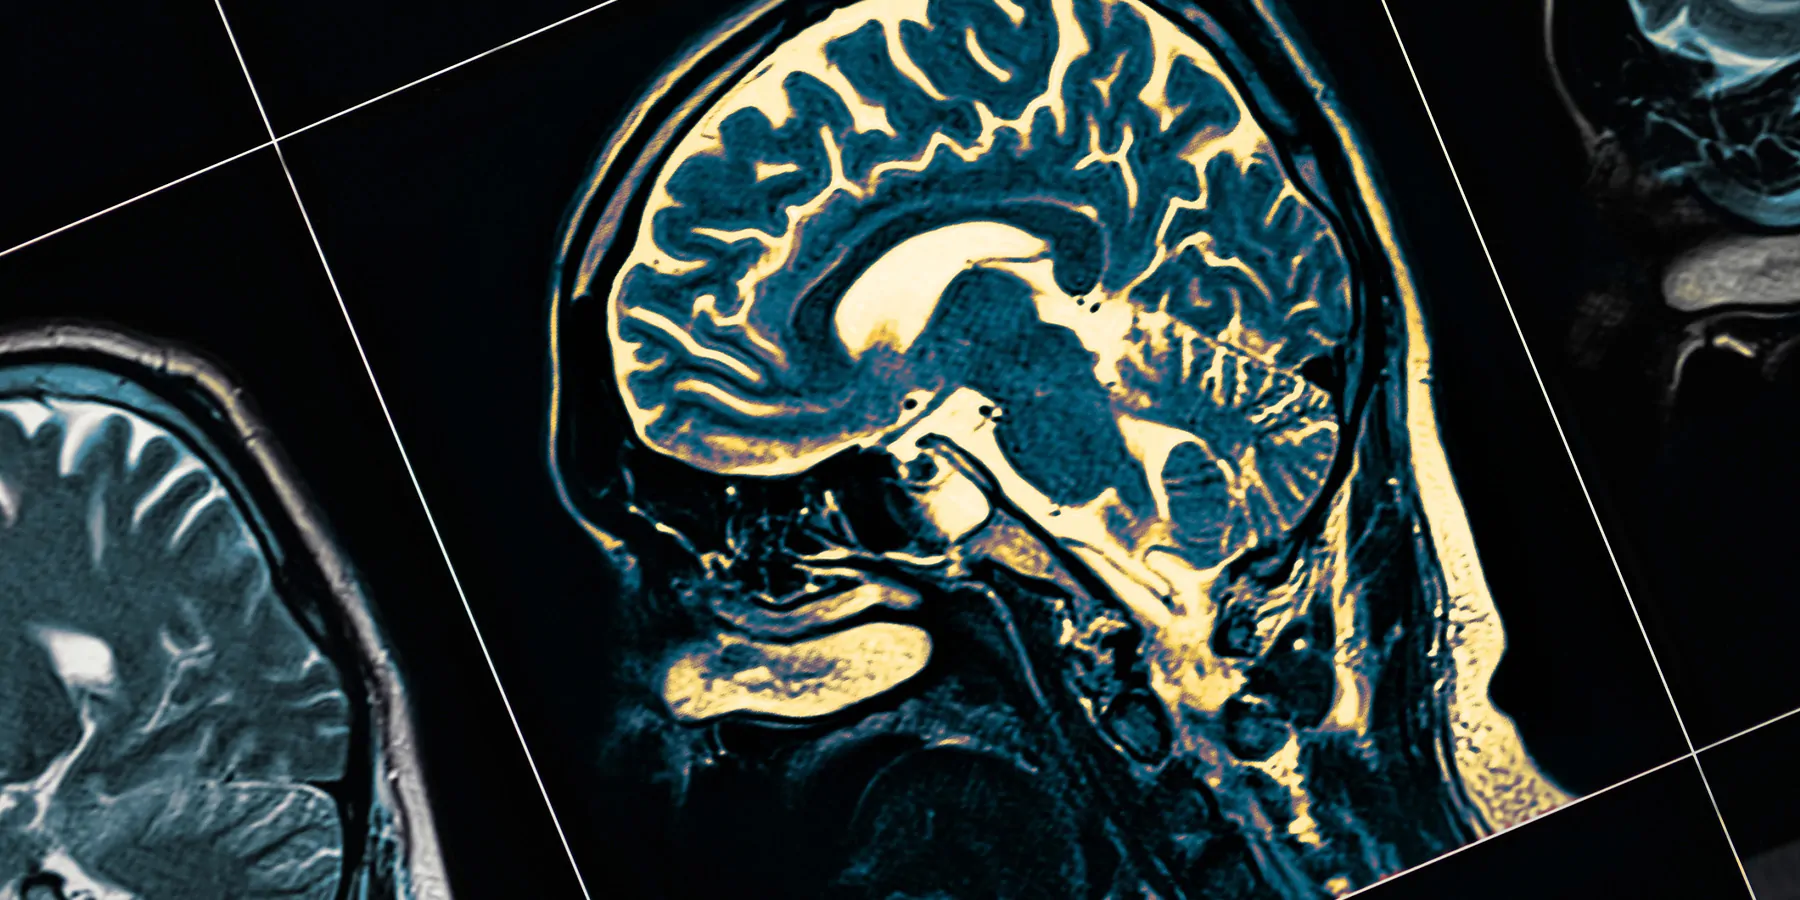

Dementia is fast becoming a global epidemic, currently affecting an estimated 50 million people worldwide. This is projected to triple by 2050—mainly driven by aging populations. Rates of dementia and associated deaths are both known to be higher in women than men.